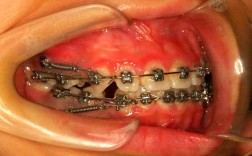

正畸导致牙龈萎缩的核心原因与口腔卫生维护密切相关,矫治器如托槽、弓丝等附件会占据牙齿表面,形成清洁死角,食物残渣和牙菌斑易堆积,进而引发牙龈炎,长期慢性炎症会破坏牙周组织,导致牙龈附着丧失,正畸施加的生物力虽有助于牙齿移动,但若加力过大或超出牙槽骨改建能力,可能压迫牙槽骨,间接引发牙龈退缩,个体因素如原有牙周基础病、刷牙方式不当(如横刷)、激素水平变化等,也会增加风险。

预防牙龈萎缩需贯穿正畸全程,分阶段采取针对性措施,正畸前应进行全面牙周评估,通过牙周治疗(如洁治、刮治)控制原有炎症,确保牙周健康;拍摄X光片检查牙槽骨状况,排除严重骨缺损者,正畸中需强化口腔卫生管理:选用正畸专用牙刷(如小头牙刷、U形刷),配合牙线穿行器清洁托槽邻面,每日至少使用牙线1次,牙缝刷清理牙间隙;推荐冲牙器辅助冲洗,清除菌斑;采用巴氏刷牙法,力度轻柔,避免损伤牙龈,定期复诊(每3-4周1次)检查牙周状况,医生可调整加力方案,避免过度施力;若出现牙龈红肿、出血,及时进行专业洁治或上药控制炎症,正畸结束后,拆除矫治器需进行全口洁治和抛光,佩戴保持器期间仍需坚持口腔清洁,防止复发。

| 正畸中 | 口腔卫生维护与炎症控制 | 选用正畸牙刷、牙线、冲牙器;每日至少刷牙2次、牙线1次;每3-4周复诊检查牙周;调整矫治力避免过大。 |